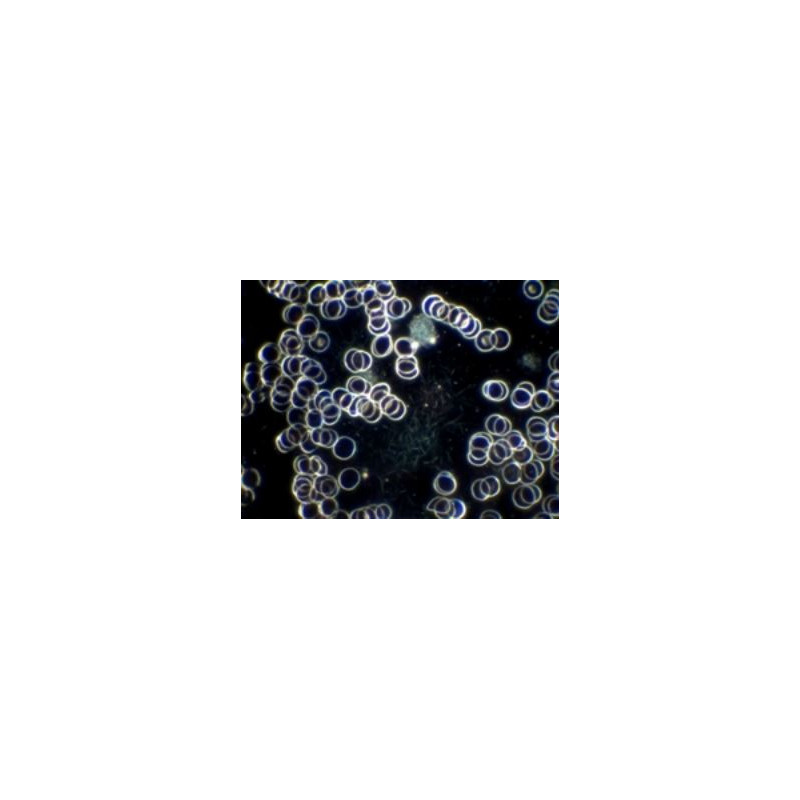

Image optimale en fond noir avec objectif SPL 100/1,25 Oel avec diaphragme à iris

Le H 600 LL HP 100 a été spécialement conçu pour l'examen du sang natif selon la méthode du Prof. Enderlein. Cette méthode permet de déterminer la qualité des cellules sanguines et du plasma. Elle garantit l'analyse de la forme et du fonctionnement des cellules sanguines ainsi que leur infestation par des micro-organismes.

Un diagnostic simple et sans erreur est obtenu grâce à un grossissement élevé, un contraste maximal et une résolution optimale.